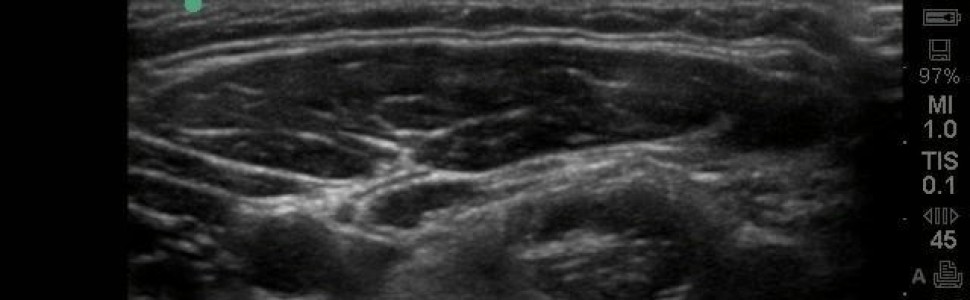

Temporomandibular disorders (TMD) are a heterogenous group of diseases which concern both temporomandibular joints (TMJ) and masticatory muscles. Choosing the best method of treatment is not an easy task for a dentist and it is often done by assessing the effectiveness of the therapy. The ability to objectively assess the progress of treatment is extremely important. Ultrasonography (US) can be used for this purpose, which allows the assessment of the TMJ and masticatory organs structures. The advantages of US include high availability, no adverse effects, high image resolution, real-time imaging, no special preparatory procedures and a relatively low cost of testing. The aim of the study was to present the possibility of diagnosing and monitoring the progress of the treatment using ultrasonography in patients with functional disorders of the masticatory system. In the case of muscle examination using ultrasound it is possible to assess their thickness and internal structure, which correlate with muscular pain. In intra-articular disorders in the ultrasound image, it is possible to assess the joint fissure, the position of the disc, the occurrence of adhesion, the width of the joint capsule, swelling of the joint and erosion of the condylar process. The use of US in the diagnosis and monitoring of TMD treatment requires further extensive research and standardization of this imaging method. Given the low cost, non-invasiveness, no side effects, no contraindications and short duration of the examination it is suggested to use US in dental practice more often.